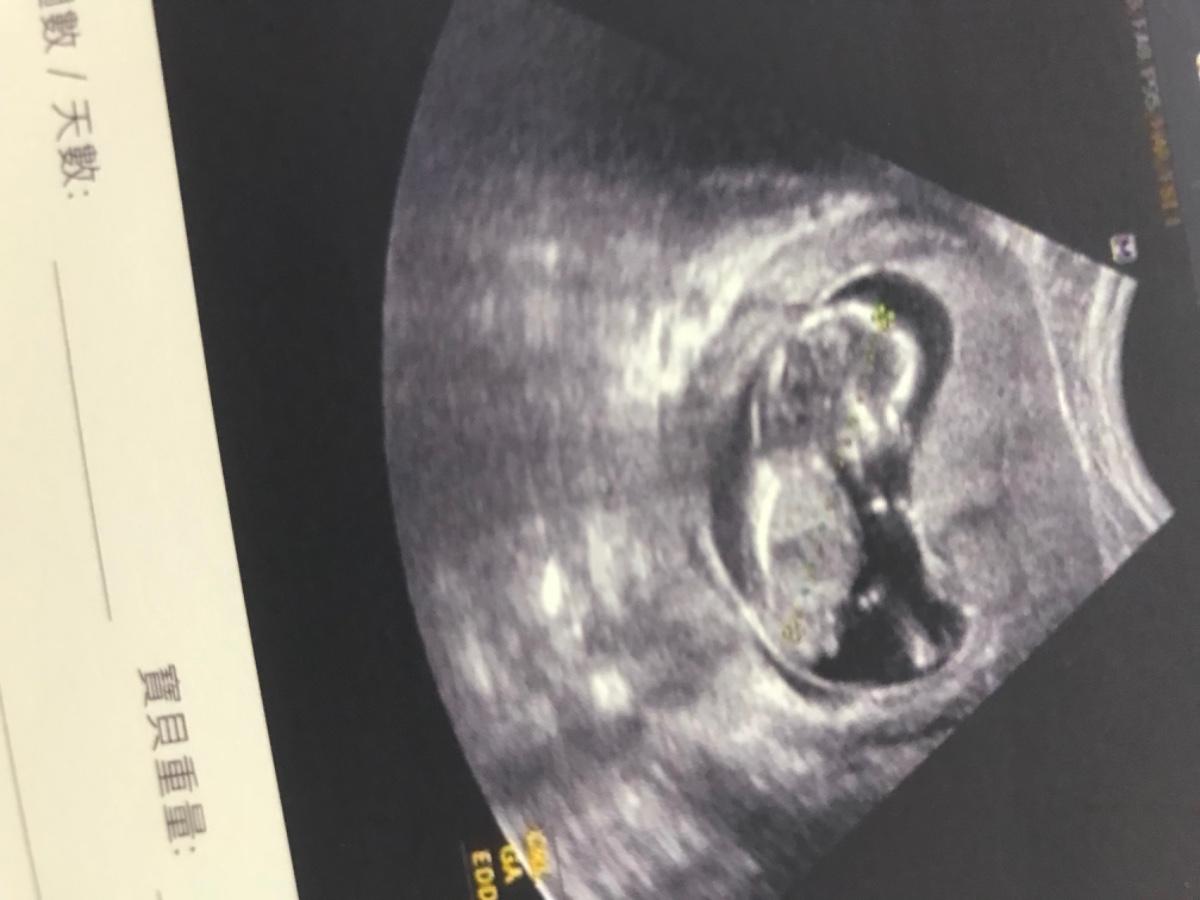

在診間門外等待的我,心情忐忑不安(一開始就先去驗尿)終於叫到我的名字!醫生開頭就說:「恭喜哦!妳懷孕了」我的眼眶真的真的泛淚,我真的快要哭出來了!接著醫生替我內診做檢查(我個人是不怕內診,因為有過不少次經驗,重點醫生也是幫我看過蠻多次)我邊看著螢幕,醫生邊跟我說,螢幕上的那個小黑點就是我的小寶寶(當時醫生預估寶寶是五週大)